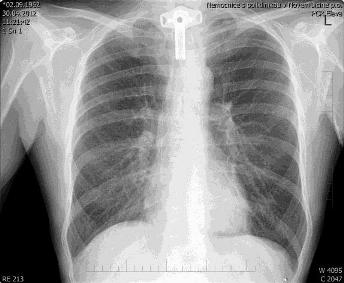

Konec katetru je umístěn v oblasti kavoatriální junkce, splňuje tedy kriteria pro centrální žilní vstup (obr. 4).

Obr. 4: Konec katetru umístěn v oblasti kavoatriální junkce.

Katetr je v oblasti vnitřní strany paže fixován bez nutnosti sutury (obr. 5). Poloha katetru je ověřena skiagraficky (obr. 6).

Obr. 5: PICC in situ. Obr. 6: Skiagrafický obraz PICC.